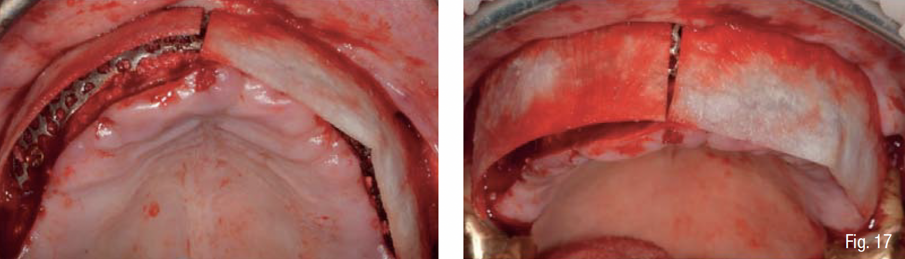

La corticale esterna del sito ricevente è stata perforata (Fig. 11) al fine di promuovere la migrazione delle cellule osteogeniche e osteoprogenitrici e la rivascolarizzazione dell’innesto osseo al di sotto della griglia. L’osso autologo del paziente è stato mescolato in rapporto 1:1 ad osso eterologo di origine bovina ad alta porosità (Zcore®, Osteogenics Biomedical, Lubbock, Texas), tutto idratato con sangue venoso periferico del paziente (Fig. 12). La griglia customizzata è stata quindi riempita con il materiale da innesto, posizionata a livello della superficie vestibolare del mascellare, e fissata con 5 mini-viti di sintesi in titanio di lunghezza 6-9 mm (BTK screw, Biotec Srl, Dueville, Vicenza, Italy), verificandone la perfetta stabilità e la conseguente assenza di micro- o macro- movimenti. Al fine di rispettare il principio di “esclusione cellulare” della GBR, al di sopra della griglia è stata applicata una membrana in collagene cross-linkato (Cytoplast RTM, Osteogenics Biomedical, Lubbock, Texas), fissata tramite chiodini di titanio sul lato vestibolare e suturata alla mucosa sul lato palatale (Figg. 13-17).